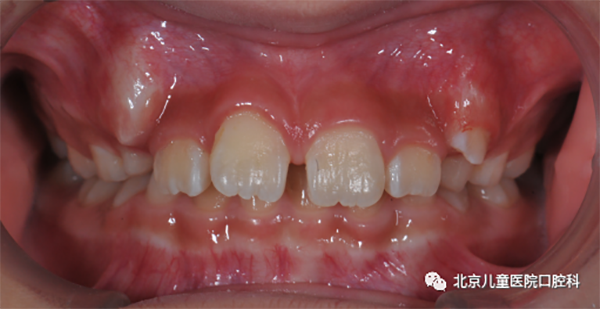

图2 上唇系带位置异常

2. 上唇系带位置异常或肥厚

须适时地行唇系带修整术。